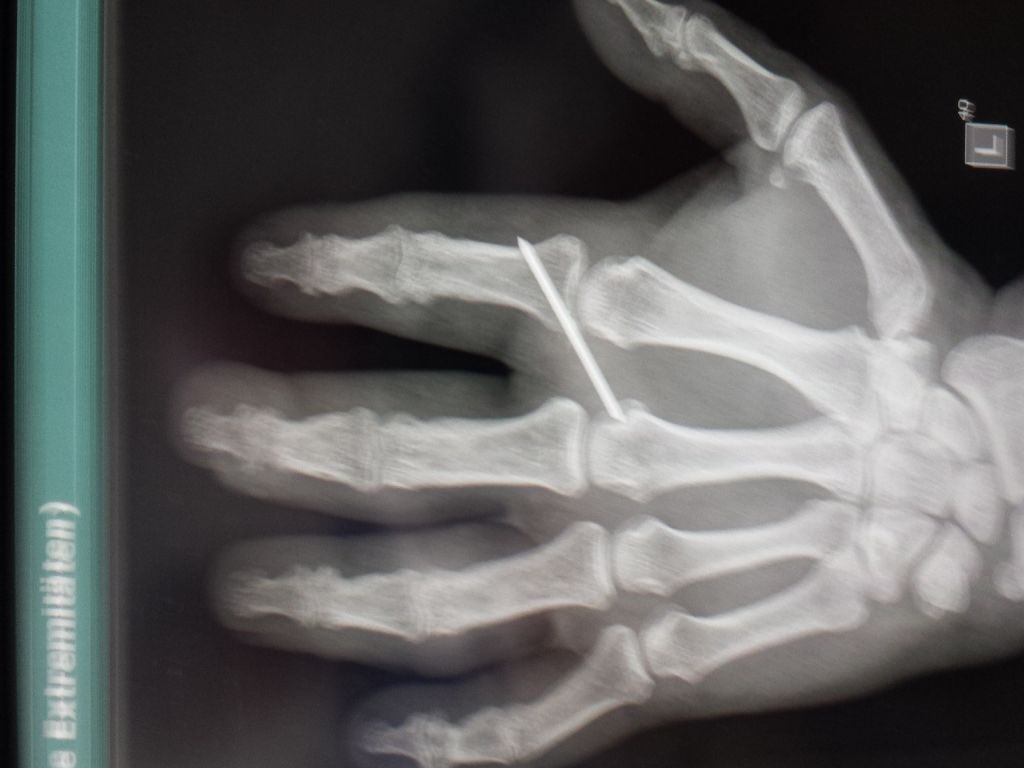

hast du eig. noch den Metallstift in deinem Finger?

Klaro, regulär bis 20.10.2014, habe morgen einen Termin zur Besprechung im KH, um 14.15°°.

Nach dem Röntgen meinte er, dass einer Entfernung des Nagels nichts entgegensteht.

Habe auch direkt ein Foto für Euch gemacht.

- k-049.jpg (62.28 KiB) 9203 mal betrachtet